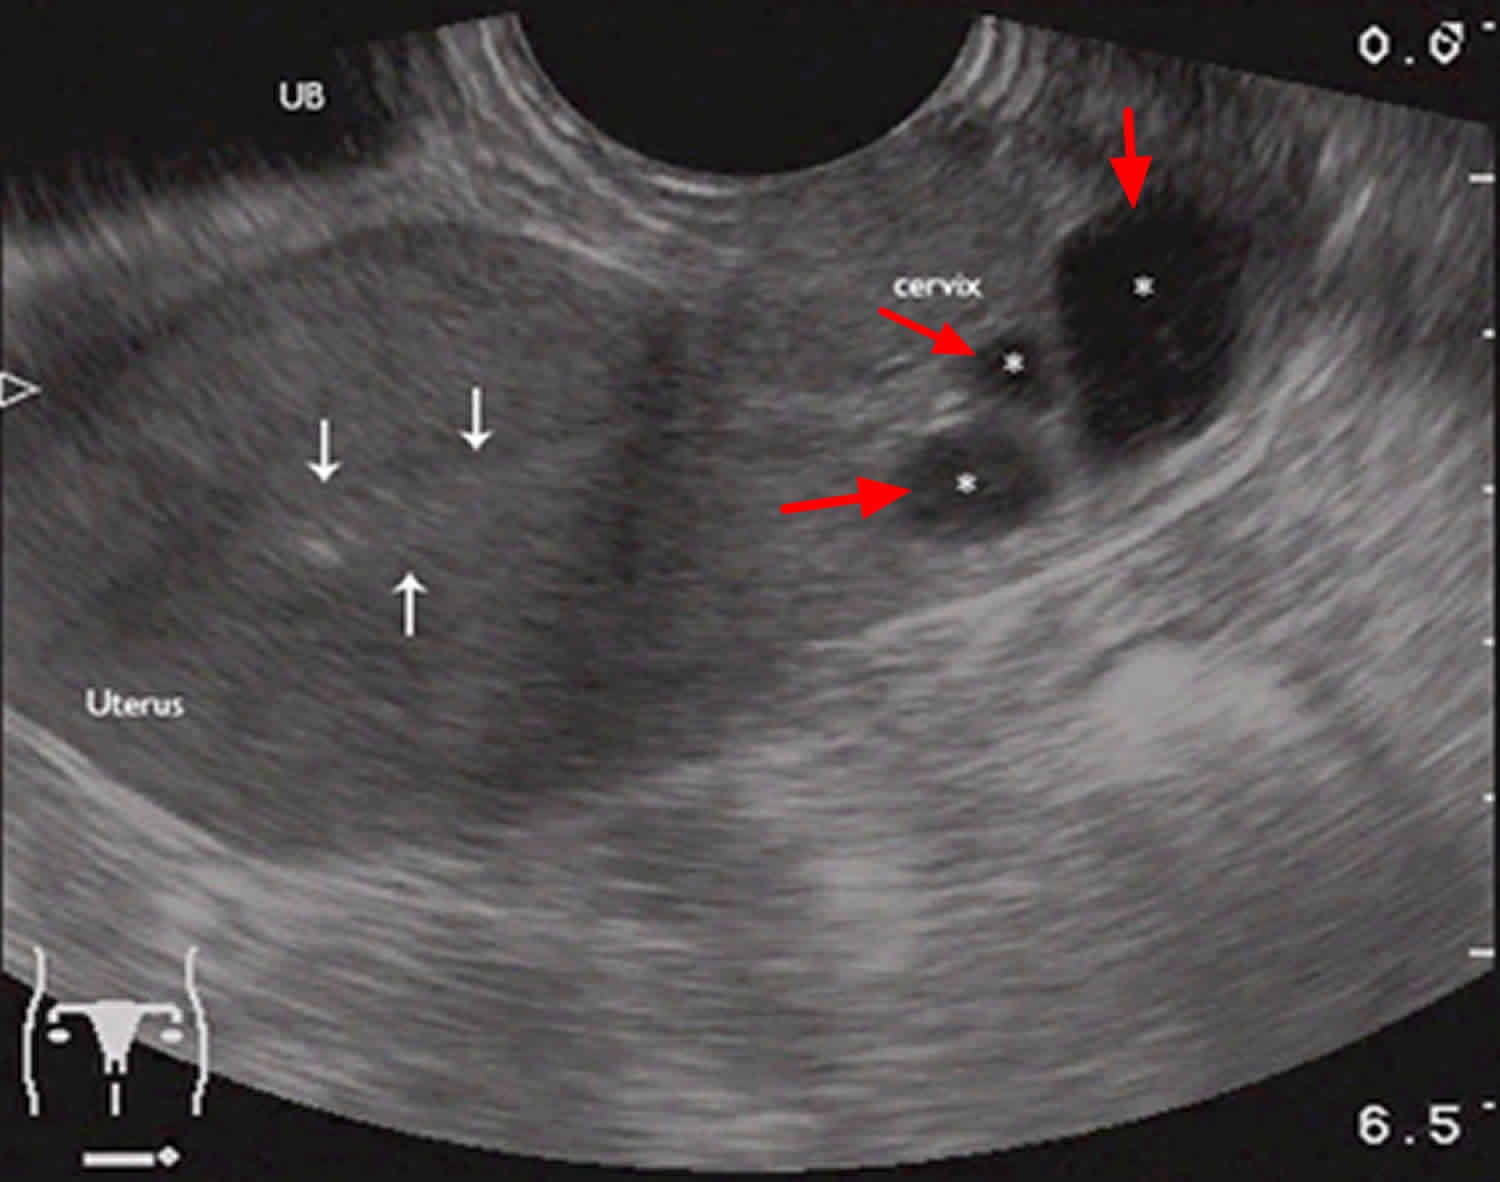

Nabothian cyst in cervix causes, symptoms & nabothian cyst treatment Can You See A Cyst In An Ultrasound 3d transvaginal ultrasound is the best possible method of assessing ovaries and evaluating the characteristics of ovarian cysts. Depending on the size of the. Can you tell if a cyst is cancerous from an ultrasound? Large ovarian cysts or pelvic masses can obscure the view of normal ovarian tissue during an ultrasound. A significant cyst or mass may. The results. Can You See A Cyst In An Ultrasound.